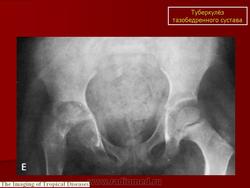

При рентгенологическом исследовании в преартритической фазе самым ранним симптомом является остеопороз, который может быть незначительным и выявляться лишь на сравнительных рентгенограммах с захватом двух тазобедренных суставов. Еще до появления туберкулезного остита могут отмечаться изменения со стороны мягких тканей в виде увеличения теней межмышечных прослоек между контурами суставной сумки и малой и средней ягодичными мышцами (симптом Ланге - Будинова). Отмечается также асимметрия костей малого таза (симптом Пинхасика), обусловленная неправильным положением больного из-за атрофии мышц, или наоборот утолщением сустава на больной стороне, или вследствие болевой контрактуры. Зная наиболее частую локализацию туберкулезных оститов вокруг тазобедренного сустава можно выявить участки нарушения костной структуры, нечеткость костных трабекул. Спустя 1,5-2 месяца выявляются очаги деструкции костной ткани с нечеткими неровными контурами, которые могут содержать множественные губчатые секвестры. Наиболее часто туберкулезные оститы располагаются в костях, образующих вертлужную впадину, реже они встречаются в шейке, и как исключение в головке бедренной кости. Причем очаги деструкции костной ткани, расположенные в вертлужной впадине, лучше выявляются на задних рентгенограммах, а очаги деструкции в шейке бедра, особенно в нижне-внутреннем отделе ее лучше выявляется на рентгенограммах с отведением бедра (по Лауенштейну). У некоторых больных наблюдается ранняя деформация ядра окостенения головки бедра в виде его увеличения.

Артритическая фаза (при переходе процесса на сустав) на рентгенограммах характеризуется усилением остеопороза, который постепенно распространяется на все кости нижней конечности. Суставная щель асимметрично суживается, больше в верхне-наружных отделах. В дальнейшем сужение суставной щели достигает значительной степени. Суставные поверхности костей теряют свои очертания, их контуры становятся нечеткими, неровными. Выявляются краевые, без четких контуров содержащие секвестры, очаги деструкции костной ткани. Последние могут вызывать значительные разрушения вертлужной впадины, головки и даже шейки бедренной кости, смещение головки бедра вверх.

В ранней фазе развития туберкулезного коксита может возникнуть необходимость в проведении дифференциальной диагностики с остеохондропатией головки бедренной кости. Клинические симптомы этих заболеваний на ранних стадиях могут быть сходны, и рентгенологическому методу принадлежит решающее значение. Однако в пользу туберкулеза свидетельствуют явления интоксикации, местные воспалительные изменения, атрофия мышц и данные лабораторных исследований. Надо отметить, что и при рентгенологическом исследовании в начальных стадиях остеохондропатия головки бедренной кости может иметь некоторые сходные симптомы с туберкулезным процессом: незначительный остеопороз костей, образующих тазобедренный сустав, смещение бедра кнаружи, деформация запирательного отверстия на пораженной стороне. Однако уже на ранних стадиях остеохондропатии суставная щель представляется расширенной. Эпифиз бедра имеет или нормальную плотность, или структура его несколько уплотнена, а на рентгенограммах с отведением бедра лучше удается выявить деформацию эпифиза и его уплощение. В дальнейшем наблюдается еще большее уплощение эпифиза, его фрагментация. Суставная щель остается расширенной.